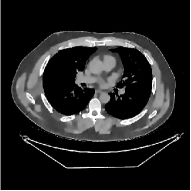

This section compares the reconstruction quality and runtime among the proposed MBIR method, PWLS-ST-, and other three MBIR methods, PWLS-EP, PWLS-DL, and PWLS-ST-. Table I shows that, for both 2D and 3D sparse-view CT reconstructions of the XCAT phantom, the proposed PWLS-ST- model outperforms PWLS-EP and PWLS-ST- in terms of RMSE. In addition, PWLS-ST- using a square transform (of size ) achieves lower RMSE than PWLS-DL using an overcomplete dictionary (of size ) for 2D sparse-view reconstructions. Fig. 3(a) and Fig. 4 show the reconstructed images for 2D and 3D phantom experiments, with different reconstruction models and different number of views. (See the corresponding error maps in the supplement.) The proposed PWLS-ST- consistently gives more accurate image reconstructions compared to other MBIR methods. Specifically, PWLS-ST- has smaller errors in the heart region (see zoom-ins in Fig. 3(a)) of 2D reconstructions than PWLS-DL and PWLS-ST-. In addition, compared to PWLS-ST-, PWLS-DL and PWLS-ST- have some ringing artifacts around the edges with high transition, e.g., edges between air and soft tissues. (See a comparison of profiles of PWLS-ST- and PWLS-ST- in the supplement.) In particular, PWLS-ST- and PWLS-DL give more visible ringing artifacts for 2D reconstruction from fewer views, and PWLS-ST- has these ringing artifacts for 3D reconstructions regardless of the number of views (see zoom-ins in Fig. 4). Table II reports runtimes of different MBIR methods in reconstructing the -views XCAT phantom scan. (FBPConvNet is a non-MBIR method and its runtime for processing a image is approximately one second with a TITAN Xp GPU.) While providing better reconstruction quality, the proposed Algorithm 1 of PWLS-ST- has shorter runtime compared to the algorithms of PWLS-DL and PWLS-ST- in Section III-A. Similar to the PWLS-EP algorithm, the reconstruction time of the PWLS-DL, PWLS-ST-, and PWLS-ST- algorithms can be further reduced by using ordered subsets [51].

Fig. 3(b) shows that when tested on the clinical scan data, the proposed PWLS-ST- method improves reconstruction quality in terms of noise and artifacts removal (e.g., see zoom-ins for soft-issue regions), and edge preservation (e.g., see zoom-ins for bone regions), compared to PWLS-EP and PWLS-ST-. Compared to PWLS-DL, PWLS-ST- achieves comparable image quality, but requires less computational complexity.

The benefit of the proposed PWLS-ST- over PWLS-ST- can be explained when there exist some outliers for some : in (12) gives equal emphasis to all sparse codes – from small to large coefficients that generally correspond to edges in low- and high-contrast regions, respectively – in estimating ; however, PWLS-ST- adjusts to mainly minimize the outliers, i.e., it may not pay enough attention to reconstruct regions with small coefficients. The histogram results in Fig. 1 reveal model mismatch of PWLS-ST- over the iterations. Fig. 3, Fig. 4, and Table I show that PWLS-ST- can moderate model mismatch, and provides more accurate reconstruction than PWLS-ST-.

| (a) 2D fan-beam CT experiments |